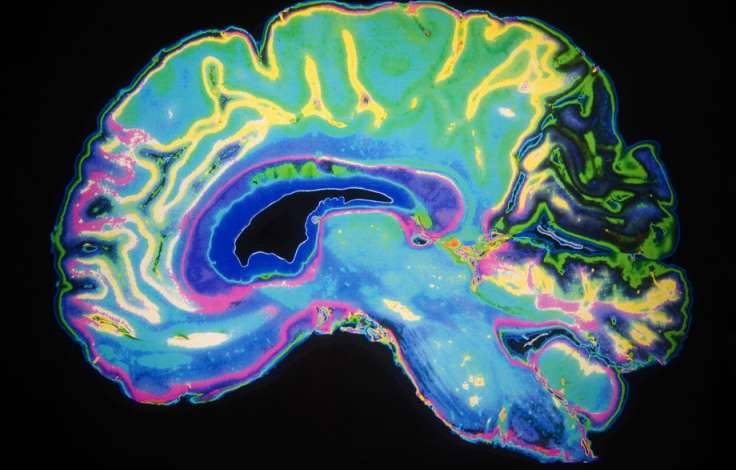

参与研究的10名病人都有早期失智症症状,比如记忆丧失、轻度认知障碍、主观认知缺损等等。接受治疗后,情况完全改变。其中一名60多岁病人的大脑海马体严重萎缩,治疗10个月后,萎缩的海马体体积竟然增大了,他的认知能力也有了改善。分享出去,让大家都看到这件事,期待失智症被彻底打败的那一天吧!